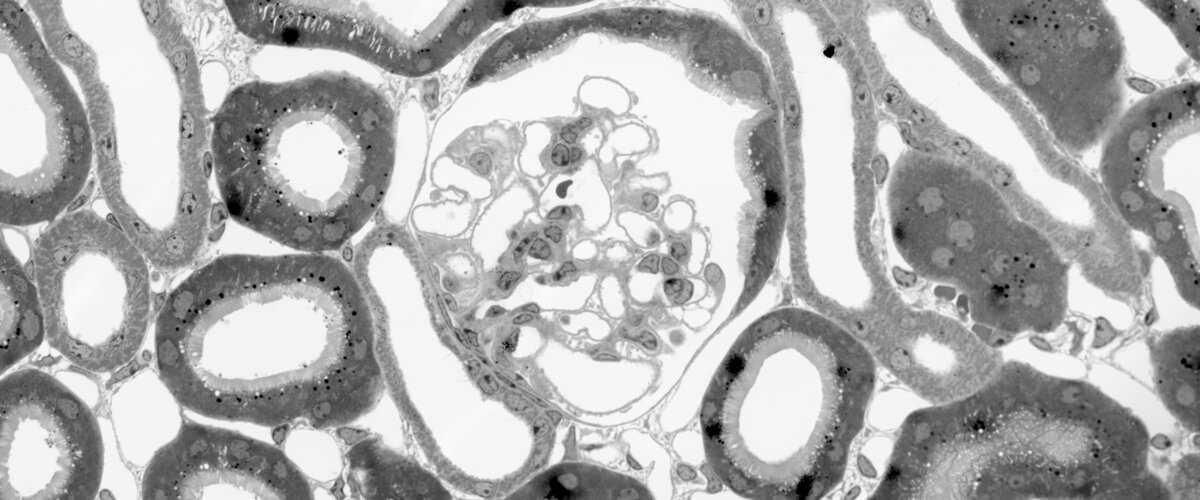

Die Rolle von podozytischem und tubulärem β-Catenin bei proteinurischen Nierenerkrankungen

Die Wnt/β-Catenin-Signalübertragung ist ein biologisch hochkonservierter zellulärer Signaltransduktionsweg, der wichtige Funktionen bei der Embryogenese, Zellproliferation, Zelldifferenzierung und Migration hat. Es wurde gezeigt, dass der Wnt/β-Catenin-Signalweg für die Regeneration und Reparatur tubulärer Schäden bei akuter Nierenverletzung essenziell ist. Im Gegensatz dazu führt eine konstante Aktivierung der Wnt/β-Catenin-Signalübertragung bei chronischen Nierenerkrankungen zum Fortschreiten der Erkrankung, sodass in diesem Fall eine Hemmung von β-Catenin schützende Wirkungen haben könnte. In diesem Projekt wollen wir untersuchen, wie wir die positive Funktion von β-Catenin sowohl im Glomerulus als auch im Tubulus fördern können, wobei wir uns insbesondere auf proteinurische Nierenerkrankungen konzentrieren.